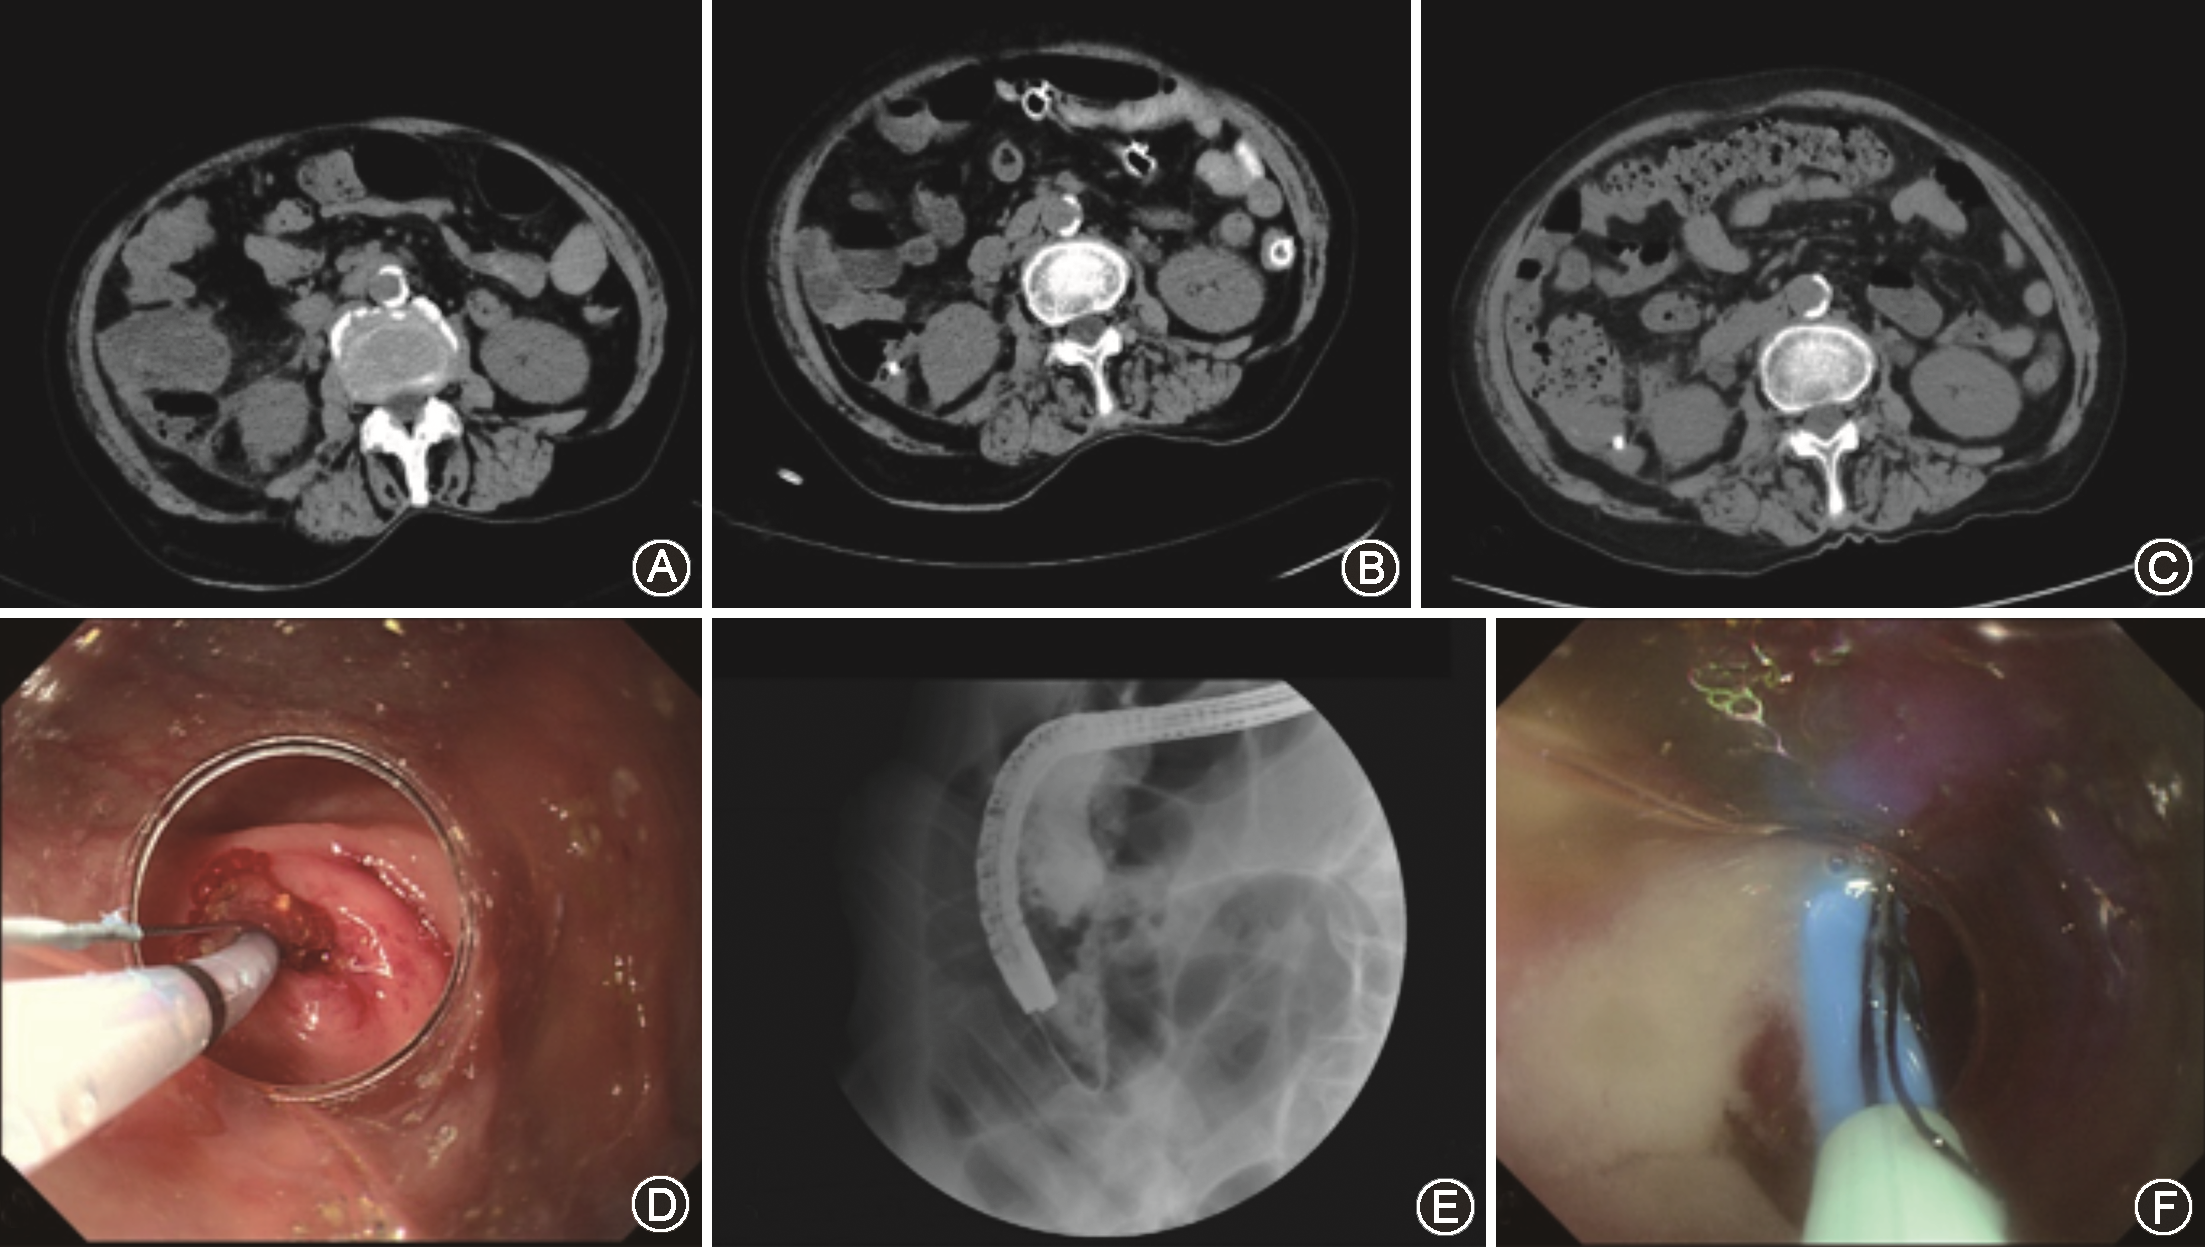

WBC:20.3×109/L,肝胆彩超提示胆囊及胆管正常范围,腹腔感染。给与常规抗生素治疗后患者腹痛减轻,但仍然持续发热,体温持续在38.5~39.2 ℃,出现谵妄。进一步腹部CT显示肝脏下方巨大低密度灶延续至右下腹肠腔及阑尾周围。胃镜检查排除消化道穿孔,肝胆彩超排除急性胆囊炎及肝脓肿。

临床诊断考虑肝下型急性阑尾炎合并阑尾周围脓肿。

通过普外科、麻醉科及消化内科共同会诊,考虑患者高龄,合并心血管疾病史,不建议急诊外科手术,决定采用内镜逆行ERAT治疗。手术经过:常规结肠镜抵达盲肠,可见盲肠及阑尾开口明显水肿,大量脓液流出;采用导丝导管技术顺利插管阑尾管腔,负压抽吸脓液后,使用水溶性造影剂在X线监视下造影提示阑尾周围脓肿。随后,生理盐水冲洗脓腔并置入一体式塑料支架(直径8.5 Fr,长15 cm)于阑尾管腔(图1)。

术后腹痛立即缓解,术后5 d症状消失出院;术后第12天复查腹部CT腹腔脓肿消失,术后2个月于门诊经结肠镜取出支架。已电话随访至7年,未复发。